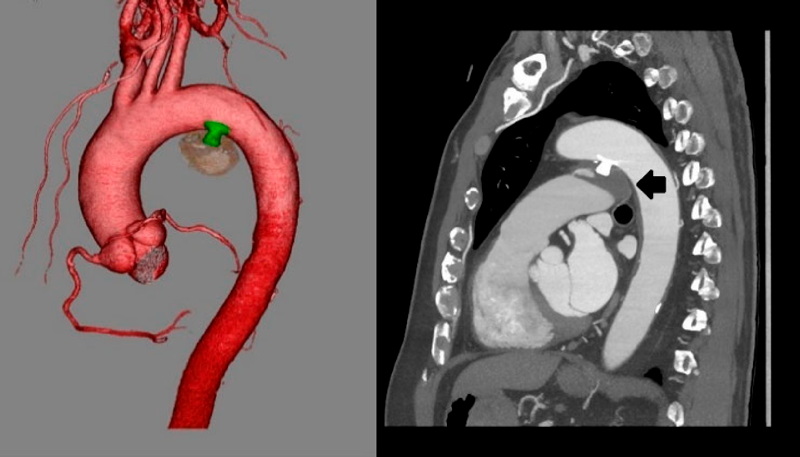

胸部造影CT

大動脈弓小彎側に入口部(径5.6 mm)をもつ最大径39 mの嚢状に拡大したDAAを認め,肺動脈側に出口部(2.2 mm)をもつ.大動脈解離なし.DAAは左主気管支と接触しているが圧排なし(Fig. 2).

Fig. 2 Contrast-enhanced chest computed tomography revealing a DAA with a maximum diameter of 39 mm, an aortic side opening measuring 5.6 mm, and a pulmonary artery side opening measuring 2.2 mm

A fistula from the minor curve of the aortic arch to the aneurysm is presented (a, b: black arrows). Drainage from the aneurysm to the main pulmonary artery is indicated (a, b: white arrows). The left primary bronchus was in contact with DAA; however, it was not compressed (c). Ao, aorta; DAA, ductus arteriosus aneurysm; LPA, left pulmonary artery; LPB, left primary bronchus.